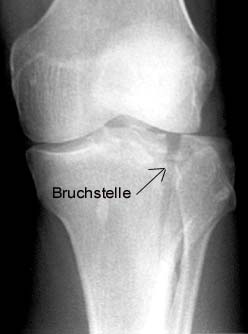

In hospital broken bone labeled Bruchstele Shin fixed with 3 screws Looking into the knee by arthroscope during surgical treatment

After exactly one half-year of untroubled riding pleasure it happens: I have an accident with my idiot-proof senior-citizen-vehicle! Suddenly my daily routine changes drastically: ambulance, university hospital, X-ray (diagnosis: long break in the tibia-plateau, the shin), a cast, knee-puncture, operation (bones fixed back in place with three screws), rehabilitation exercises and laboriously learning to walk again with crutches. A total of 12 days in the hospital and then at first twelve weeks of not being allowed to put more than 10 kg on the leg, otherwise the bones will break again and the whole painful routine will start from the beginning.